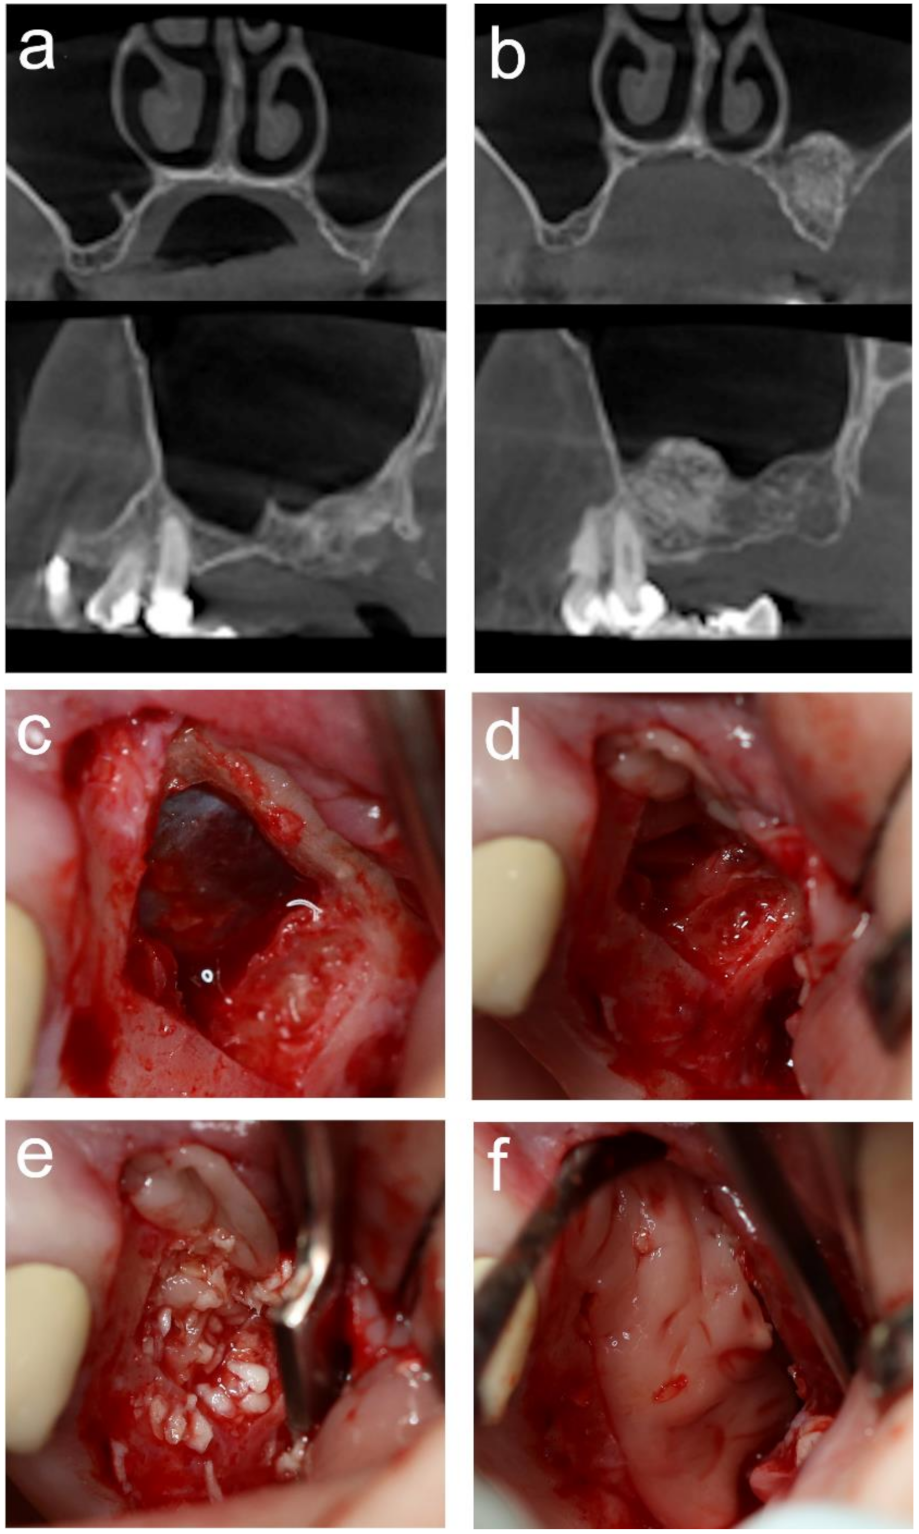

2.6. MSA

2.7. Implant Placement

3.2. MSA